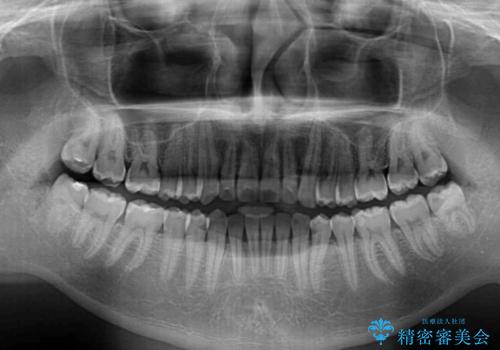

ワイヤー装置での上下前歯の部分矯正

部分矯正は咬み合わせが不安定になったり、スペースができてしまったりと、適用となる患者様は極めて限られますが、こちらの方はスムーズに治療を終えることができました。